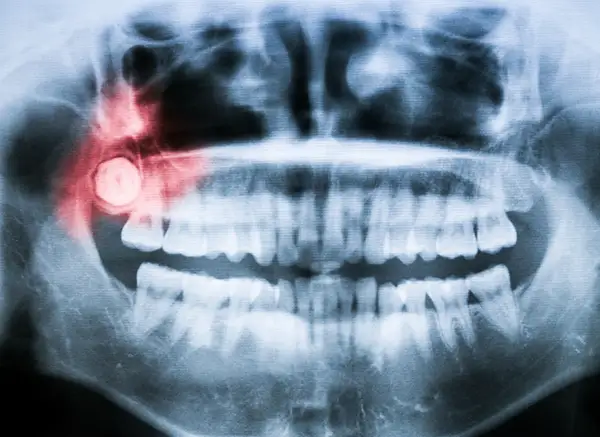

A panoramic dental X-ray with a highlighted area showing an impacted and inflamed wisdom tooth causing pain. Wisdom teeth removal is a common dental procedure designed to protect your long term oral health and prevent future complications. Wisdom teeth, also known as third molars, typically emerge during the late teen or early adult years. While some people experience no issues, many patients benefit from proactive tooth extraction to reduce discomfort, crowding, and infection risk. Working with Lakewood Dental Arts, an experienced Lakewood dentist, helps ensure the process is safe, comfortable, and tailored to your individual needs.